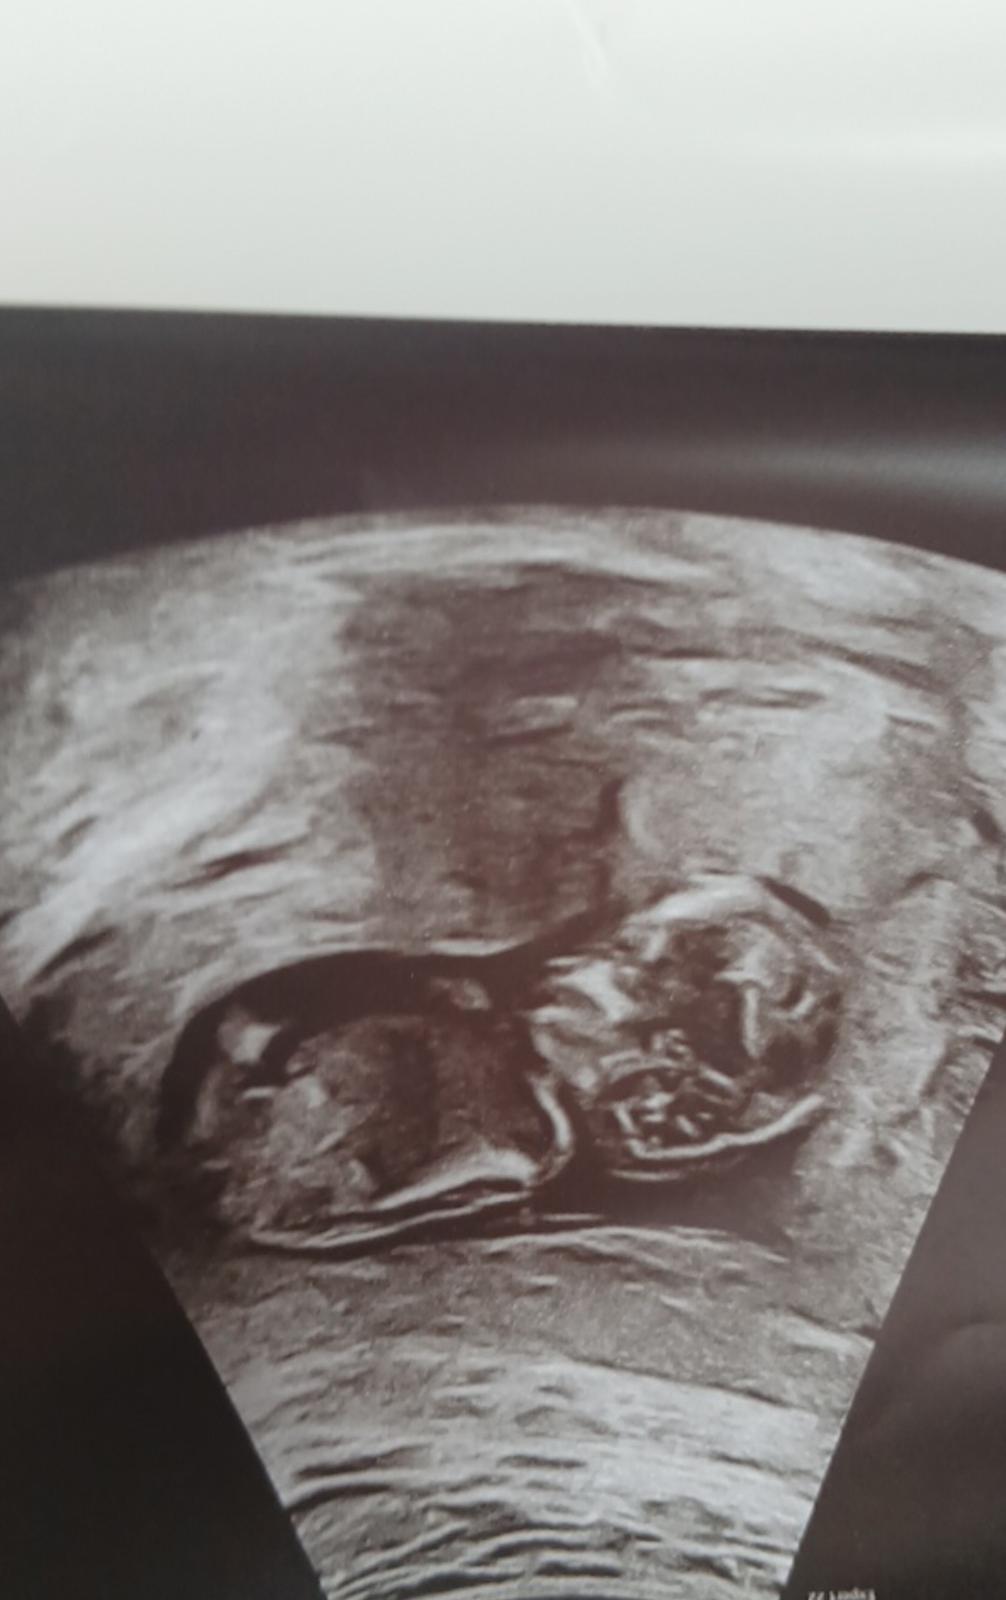

byl by možný odhad podle fotky z ultrazvuku?

Mně se zdá, že tam pindík je, ale nejsem si jistá.

omlouvám se, ale z této fotografie nic určit nelze. Inkriminovaná oblast na snímku vůbec zachycena není.☹